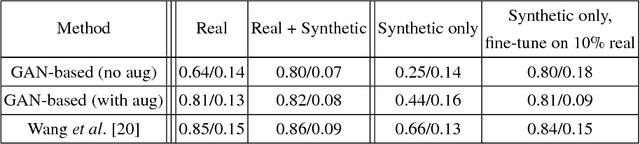

Data diversity is critical to success when training deep learning models. Medical imaging data sets are often imbalanced as pathologic findings are generally rare, which introduces significant challenges when training deep learning models. In this work, we propose a method to generate synthetic abnormal MRI images with brain tumors by training a generative adversarial network using two publicly available data sets of brain MRI. We demonstrate two unique benefits that the synthetic images provide. First, we illustrate improved performance on tumor segmentation by leveraging the synthetic images as a form of data augmentation. Second, we demonstrate the value of generative models as an anonymization tool, achieving comparable tumor segmentation results when trained on the synthetic data versus when trained on real subject data. Together, these results offer a potential solution to two of the largest challenges facing machine learning in medical imaging, namely the small incidence of pathological findings, and the restrictions around sharing of patient data.